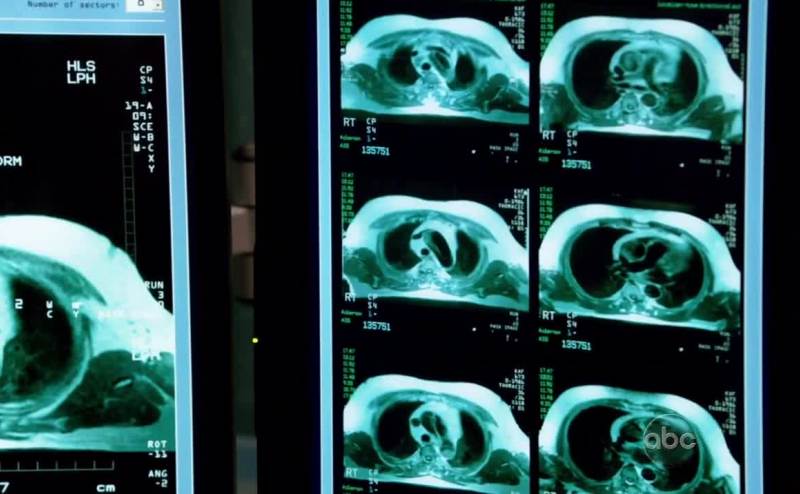

CT scan shows he's got a ruptured diaphragm.

It's like a hole. He probably injured it

When he was thrown from the car as a child.